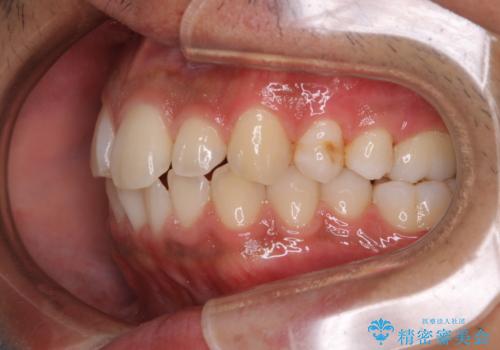

矯正をスタートする前にクリーニングを行いました。PMTC60分コースを行いました。

10年ぶりのクリーニングのため着色や歯石、プラークの量は多めでした。